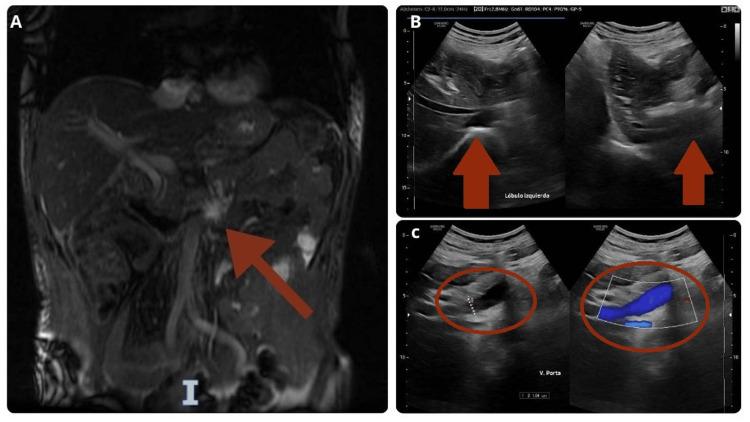

Drug-induced liver injury (DILI) is a rare condition characterized by hepatotoxic damage, identified through the elevation of liver function tests associated with a specific drug. Statins are among the medications linked to DILI, although this association is infrequent. Recently, reports and case series have described a relationship between atorvastatin-induced DILI and autoimmune hepatitis (AIH), two conditions not commonly associated. Because there are no established clinical or diagnostic criteria for this overlap, recognition is complex and relies on the clinical course, a timeline of causality, and the exclusion of alternative diagnoses. This report presents the case of a patient in the seventh decade of life who developed atorvastatin-induced DILI, meeting the diagnostic criteria for AIH. We discuss the therapeutic approach and review the relevant literature on this rare association.

药物性肝损伤(DILI)是一种以肝毒性损伤为特征的罕见病症,通过与特定药物相关的肝功能检查指标升高得以确诊。他汀类药物是与DILI相关的药物之一,尽管这种关联并不常见。最近,报告和病例系列描述了阿托伐他汀诱导的DILI与自身免疫性肝炎(AIH)之间的关系,这两种病症通常并无关联。由于对于这种重叠情况尚无既定的临床或诊断标准,识别过程较为复杂,依赖于临床病程、因果关系时间线以及排除其他诊断。本报告介绍了一位七十多岁患者的病例,该患者发生了阿托伐他汀诱导的DILI,符合AIH的诊断标准。我们讨论了治疗方法并回顾了关于这种罕见关联的相关文献。